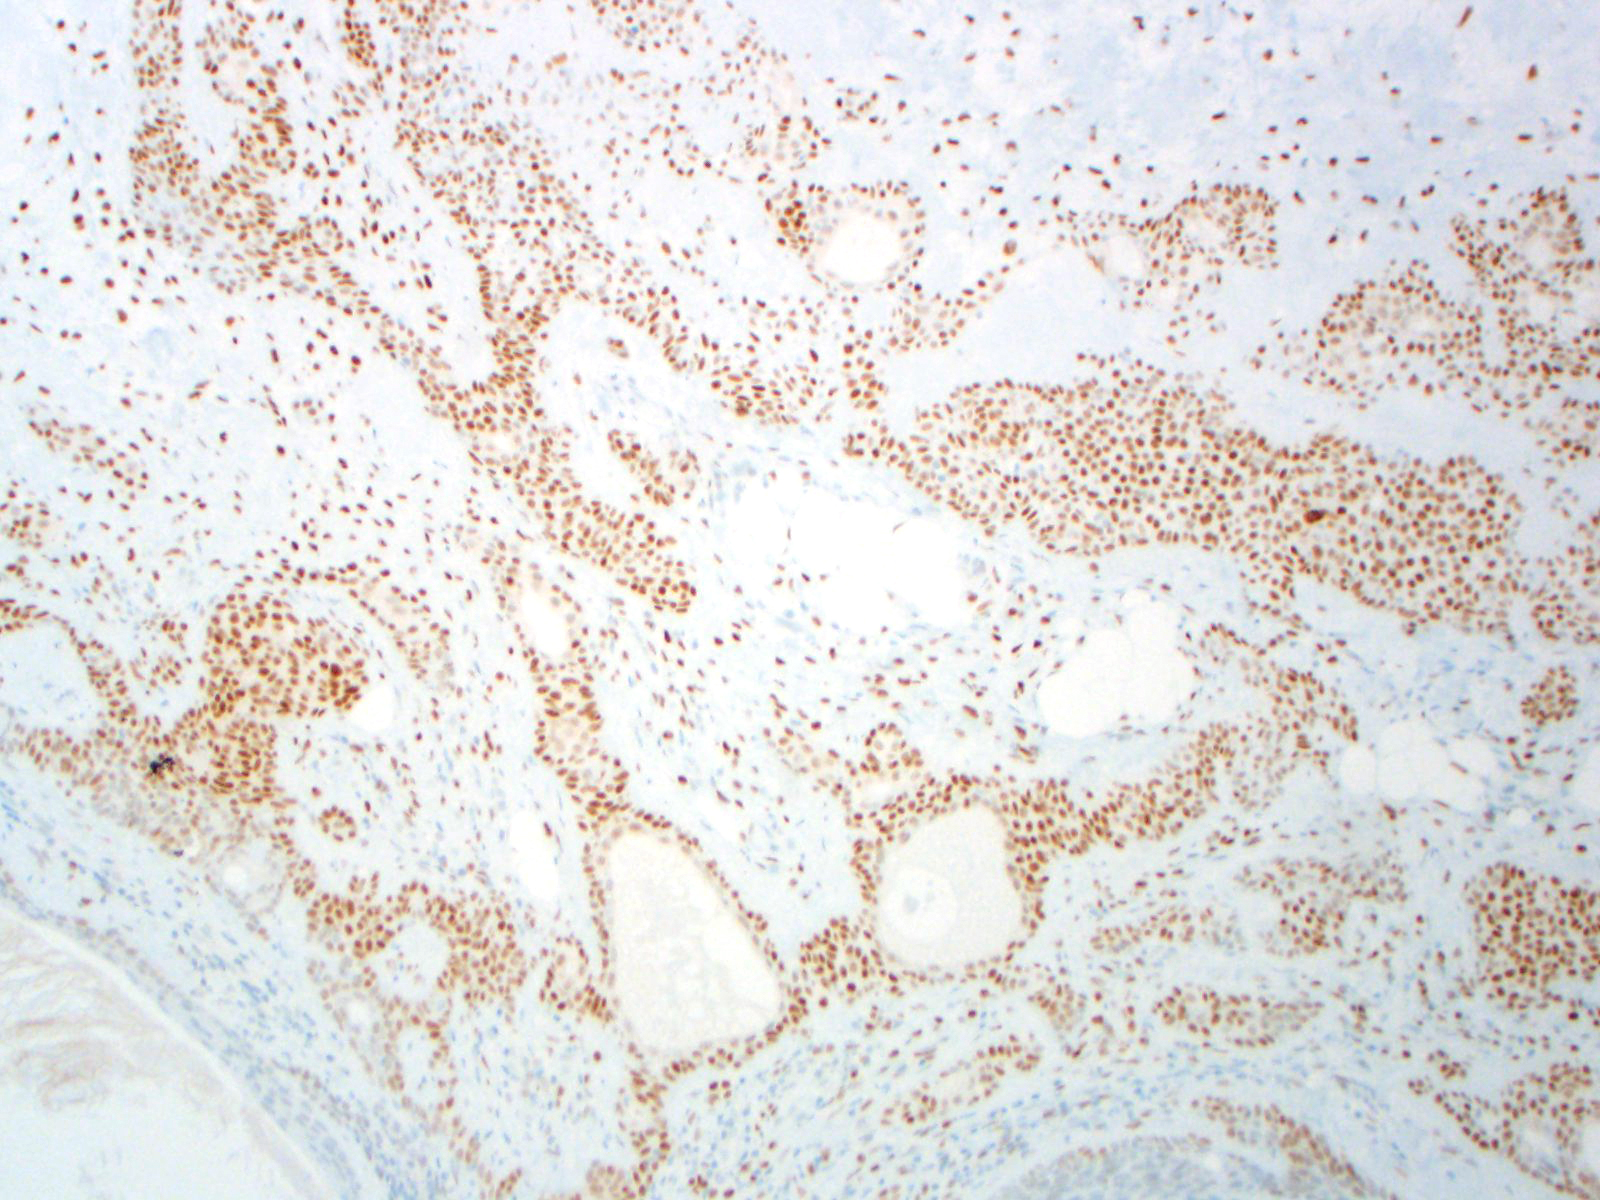

BCOR-associated tumors, including: BCOR-CCNB3 sarcoma, BCOR-MAML3 sarcoma, high-grade endometrial stromal sarcoma (ESS) harboring ZC3H7B-BCOR or BCOR internal tandem duplications (ITD), undifferentiated round cell sarcoma of young children harboring BCOR ITD, clear cell sarcoma of the kidney (CCSK) harboring BCOR ITD; EP300-BCOR pediatric glioma

Ewing sarcoma, CIC sarcoma, other sarcomas lacking BCOR alterations

Staining Pattern

Nuclear

| High-grade ESS |

| BCOR-CCNB3 sarcoma |

| Ewing sarcoma |